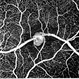

- maculoschisis, foveoschisis

- HD 6x6 OCT-Angiography Structural View of the Deep Inner Retina